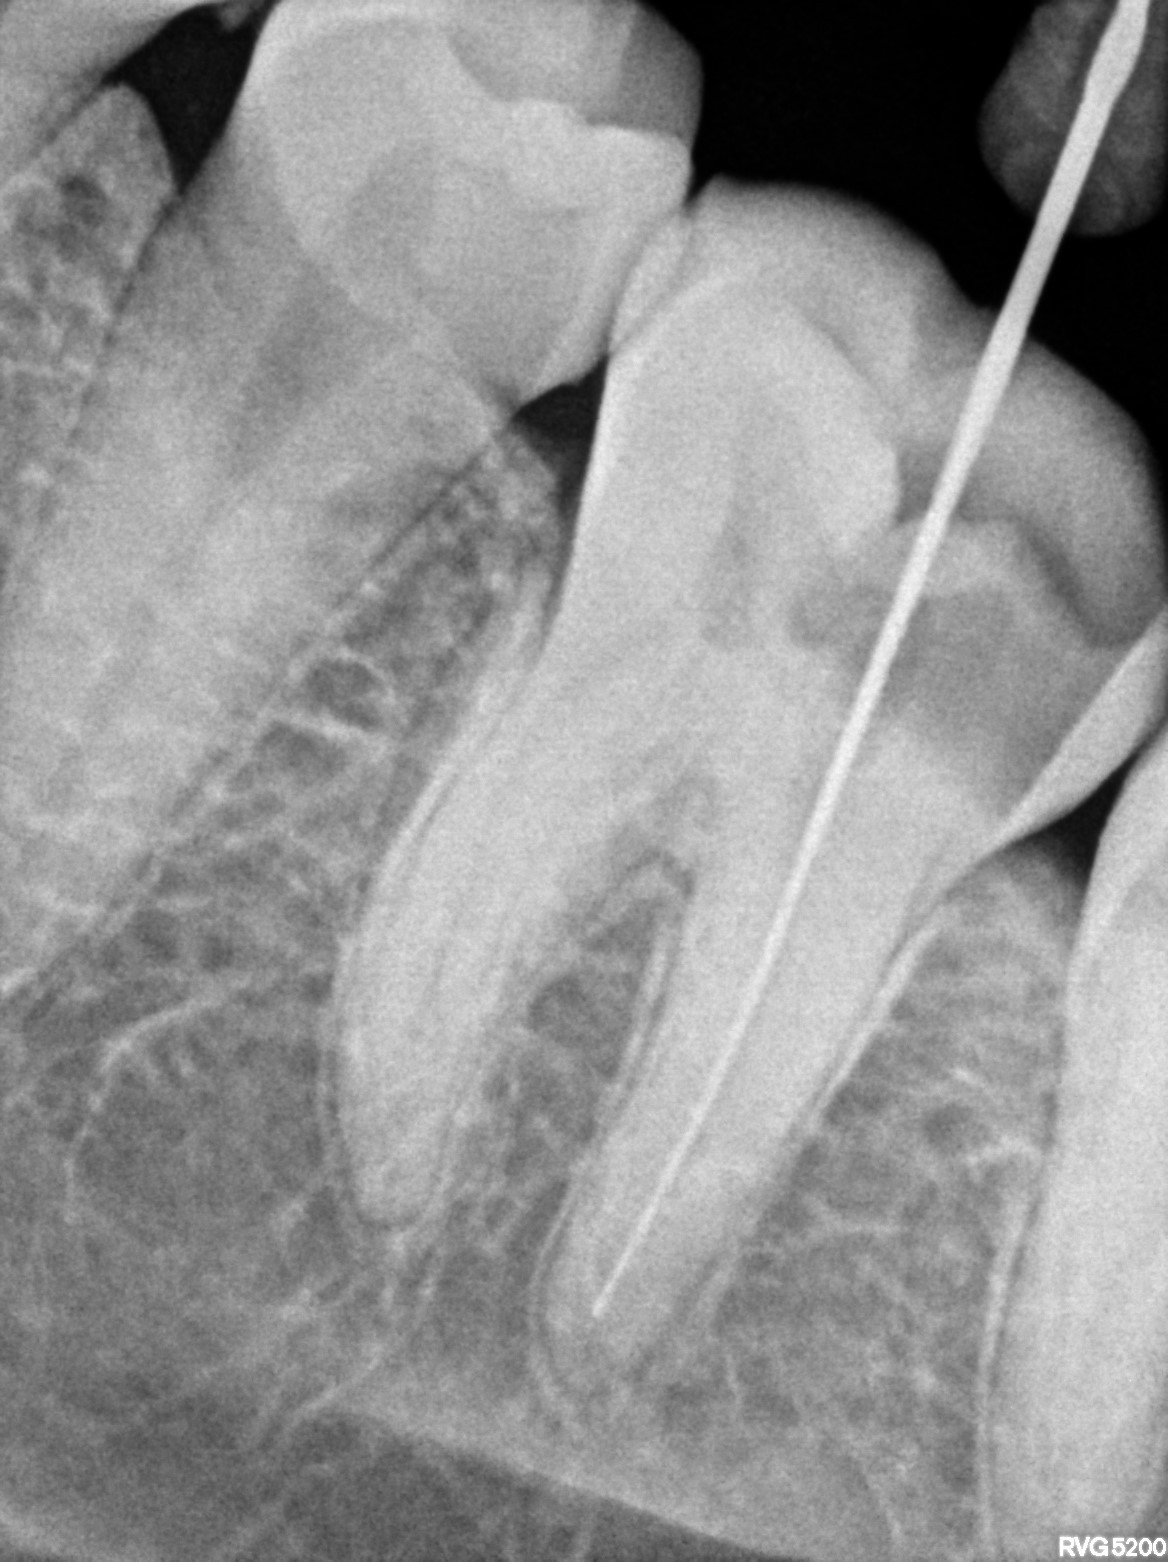

Dental Radiographs FHIR: DocumentReference · LOINC 24641-7

xray_1772613109_4.jpg

24641-7